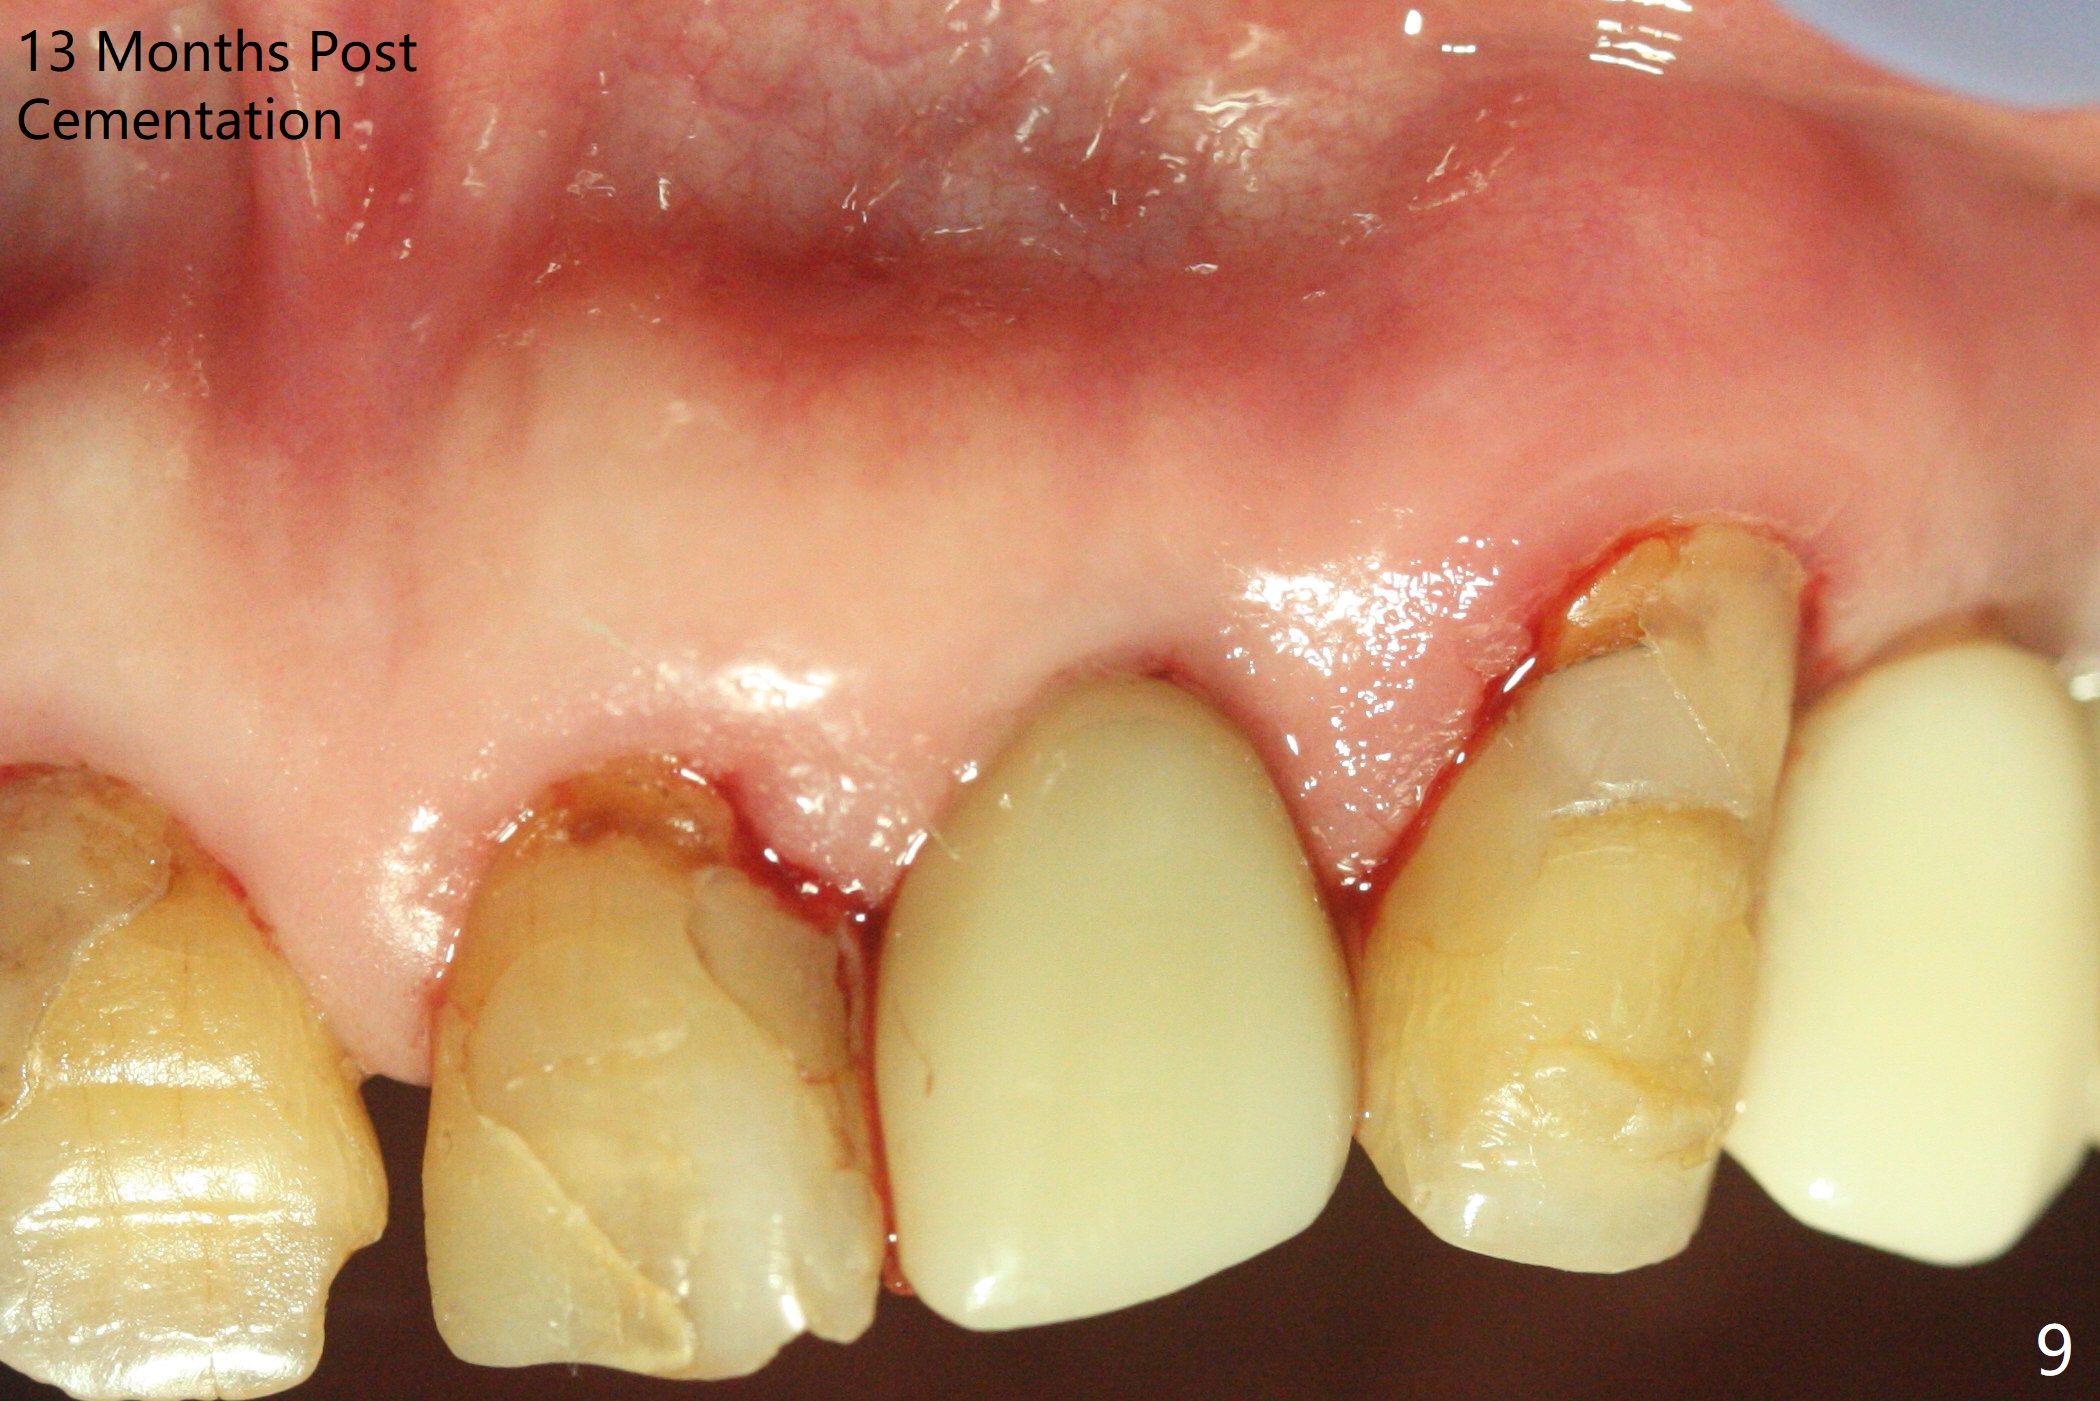

After undersized drilling in depth at #10 (2.2x13 mm (10.5 mm offset), Fig.1), a 2.5x13 mm 1-piece implant is placed (Fig.2,3), as compared to the design (Fig.3'). Following 3 more turns of the implant (~ 20 Ncm), bone graft and heavy buccal reduction of the coronal end of the abutment, an immediate provisional is bonded to the tooth #9 (Fig.4) and splinted to the tooth #11 with a twisted wire (Fig.5). To increase stability and reduce reduction, a 3 mm 1-piece implant could be used with 15 degree abutment. The implant remains stable 5 months postop (Fig.6). The implant seems to be flexible before heavy occlusal reduction; note the periimplant micro-space (Fig.7). The patient is a bruxer. The implant crown seems to be minimally mobile 2 months post cementation (Fig.8, without treatment). 牙冠粘固后1年1个月软硬组织正常(图九)。